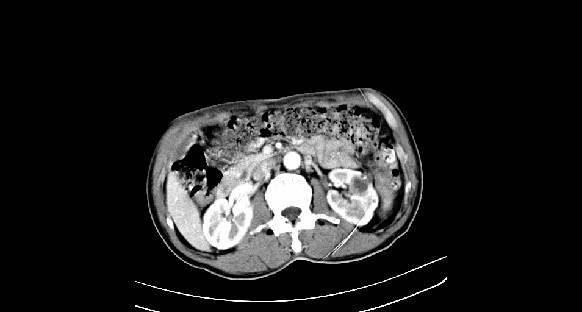

男性,70岁,体检b超发现左肾占位,请各位战友发表一下观点

左肾有两个病灶,且较大的病灶内可见点状钙化灶,增强扫描边缘也是呈渐进性强化,中央部分未见明显强化

肾癌较肾aml可能大,建议mri,若t2明显高信号者则肾癌基本诊断明确。